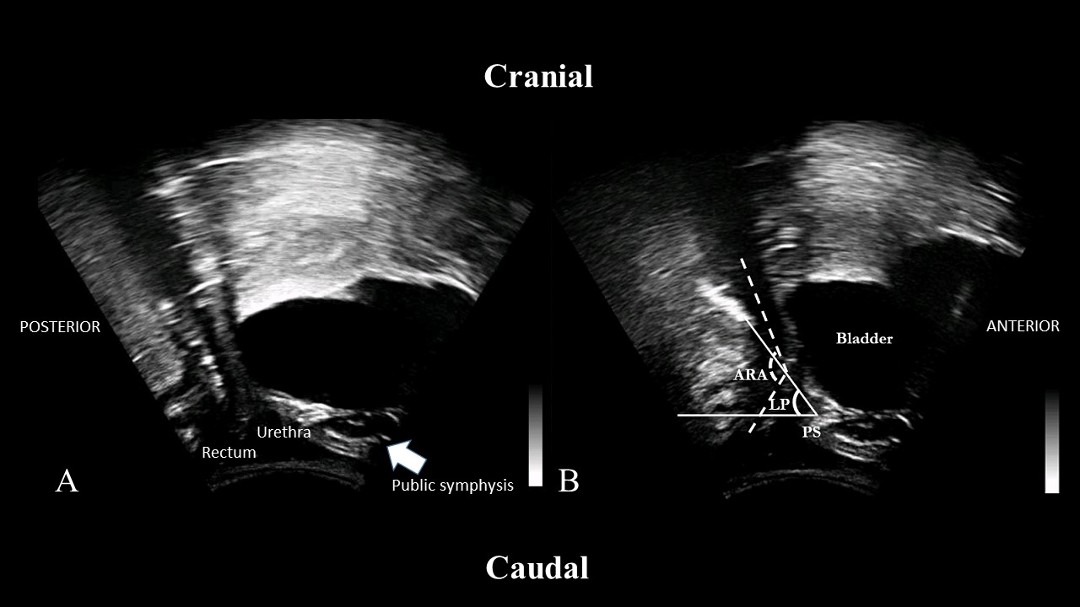

Figure 2 Figure 2. Transperineal US image of PFM at Rest (A) and during INNOVO NMES (B)

Ten healthy continent women aged 23 – 57 years gave written informed consent and participated in this study. Inclusion criteria included women 18 years or older and the ability to perform a PFM contraction. Exclusion criteria included confirmed pregnancy, neurological disease, pelvic organ prolapse, lumbopelvic surgery, recurrent urinary tract infections, and cardiac pacemaker. A bladder-filling protocol facilitated the delineation of structures during transabdominal ultrasound imaging (TAUS).  The magnitude of bladder base displacement (BBD) was measured in centimeters (cm) under three conditions in standing: pre-NMES volitional contractions, INNOVO NMES contractions, and post-NMES volitional contractions with at least a 5-minute washout period between conditions.   INNOVO shorts consist of eight embedded electrodes, with a cumulative stimulating surface area of 1200cm2 with a maximum current density of 0.189 mA/cm2. The electrodes are positioned bilaterally around the pelvis, anterior and posterior thighs. INNOVO uses patented multipath stimulation delivered via a pulsed, symmetrical, rectangular biphasic waveform at 50Hz. A pulse duration of 620µs was delivered for 5 minutes (on:off time of 5sec:5sec), resulting in 30 elicited PFM contractions.   Participants were blinded to ultrasound imaging and verbally cued to perform volitional PFM contractions pre and post-INNOVO NMES. No verbal cues were given during INNOVO NMES, which was delivered at each participant's maximum tolerable amplitude (mA) to elicit a PFM contraction confirmed by a cranial displacement of the BBD observed with TAUS.